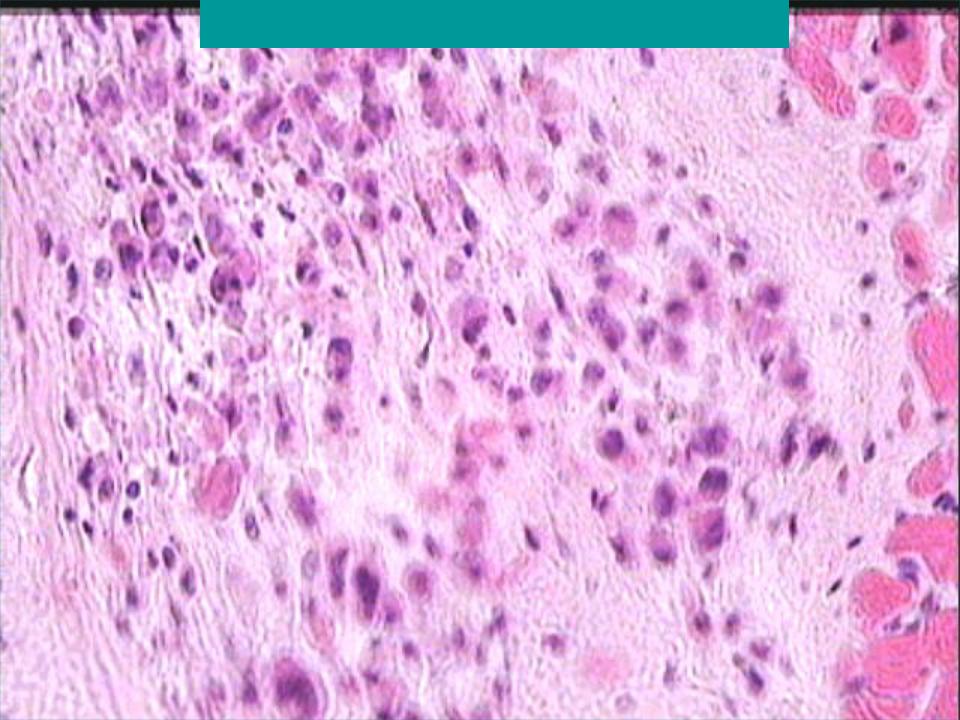

Межуточный миокардит: гистологические исследования